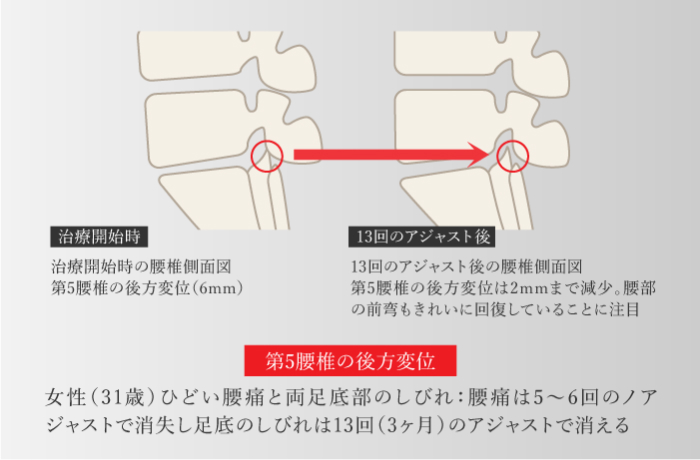

腰椎が後方にシフトしてしまっているために症状がでます。